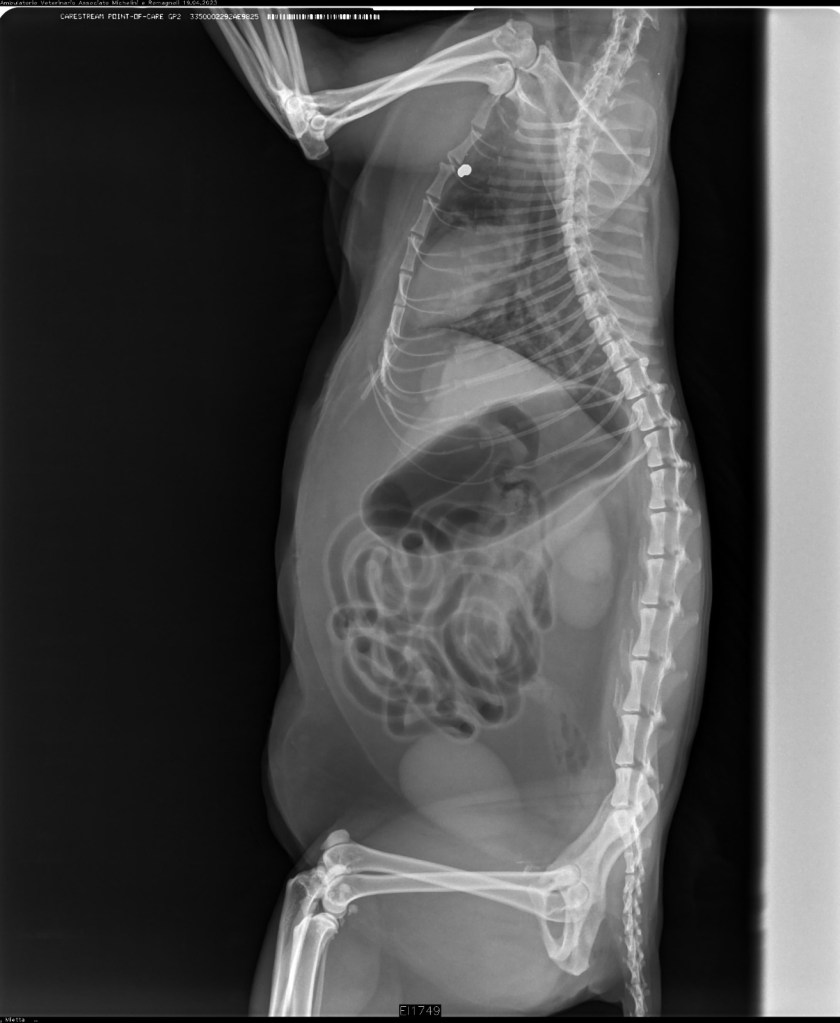

Mia viveva in casa con la sua famiglia e un altro gatto. Quando è arrivata chiedendo conforto, la famiglia era titubante proprio per via della presenza dell’altro felino. Ma Mia ha conquistato il loro cuore e un posto in casa. Qualche giorno fa la sua mamma umana si è accorta che stava male e l’ha portata dal veterinario. Le lastre hanno rivelato l’atroce verità: qualcuno aveva sparato alla gattina con una carabina. Per evitare di farla morire tra atroci sofferenze, hanno dovuto praticarle l’eutanasia.